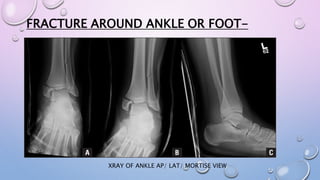

FRACTURE AROUND ANKLE OR FOOT-

XRAY OF ANKLE AP/ LAT/ MORTISE VIEW

XRAY OF FOOT BP/OBLIQUEXRAY OF CALCANEUM- CALCANEUM VIEW

BELOW KNEE SLAB

 EXTEND FROM TIBIAL TUBEROSITY

TO THE BASE OF THE TOE

 ANKLE IN NEUTRAL POSITION